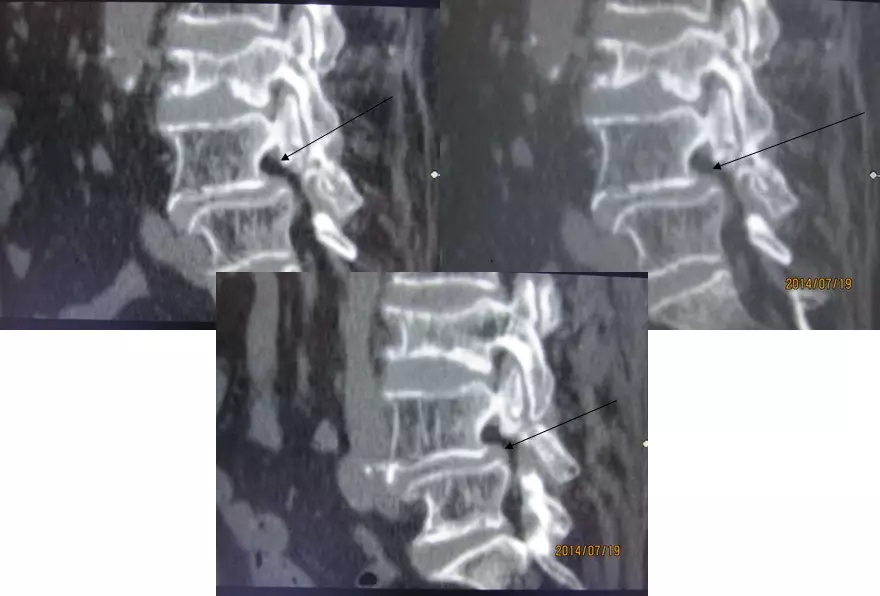

4.滑脱、峡部裂

病因分类

发育不良

缺血

退变

创伤后

代谢性

医源性

分级

I:滑移<25%

II:25%<滑移<50%

III:50%<滑移<75%

IV:75%<滑移<100%

V:滑移>100%

腰椎前滑脱I度

椎弓峡部裂